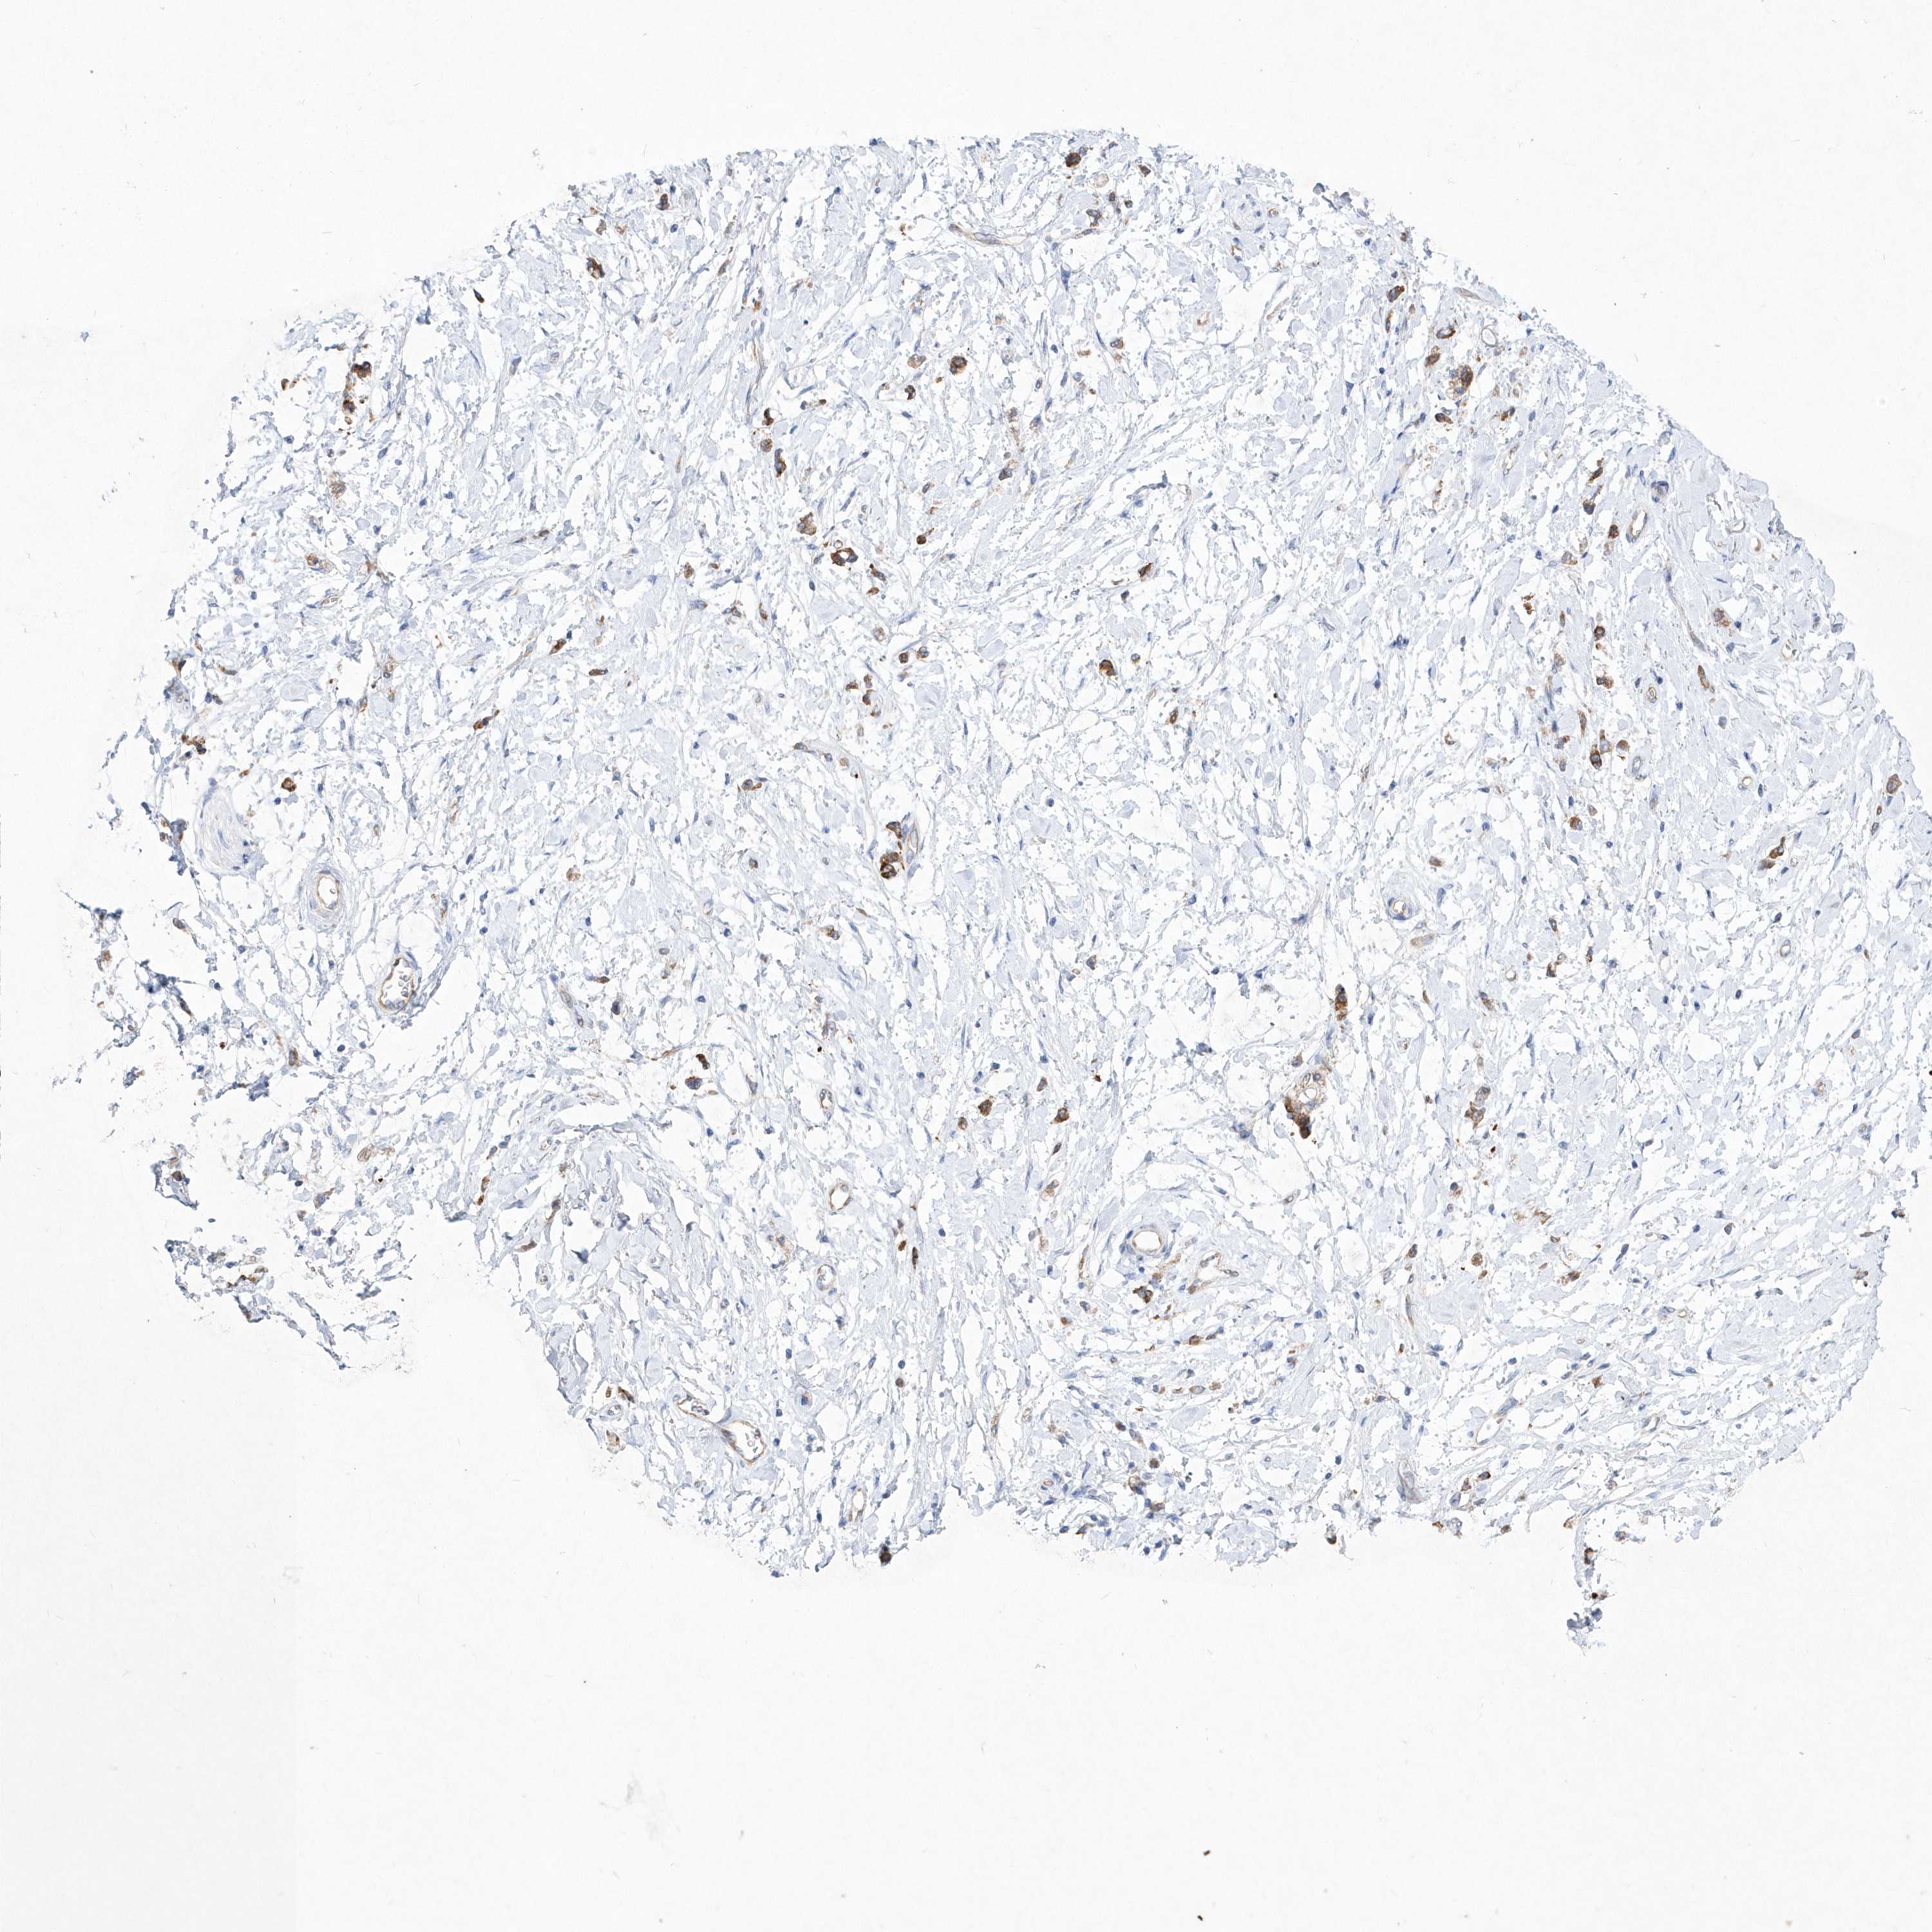

STOMACH CANCER - Protein expressioni

A mouse-over function shows sample information and annotation data. Click on an image to view it in a full screen mode. Samples can be filtered based on level of antibody staining by selecting one or several of the following categories: high, medium, low and not detected. The assay and annotation is described here.

Note that samples used for immunohistochemistry by the Human Protein Atlas do not correspond to samples in the TCGA dataset.

Antibody stainingi

Antibody staining in the annotated cell types in the current human tissue is reported as not detected, low, medium, or high, based on conventional immunohistochemistry profiling in selected tissues. This score is based on the combination of the staining intensity and fraction of stained cells.

Each image is clickable and will lead to virtual microscopy that enables deeper exploration of all samples and also displays staining intensity scores, fraction scores and subcellular localization as well as patient and tissue information for each sample.

Antibody HPA031172

Staining

High

Medium

Low

Not detected

Intensity

Strong

Moderate

Weak

Negative

Quantity

>75%

75%-25%

<25%

None

Location

Nuclear

Cytoplasmic/membranous

Cytoplasmic/membranous,nuclear

Adenocarcinoma, NOS